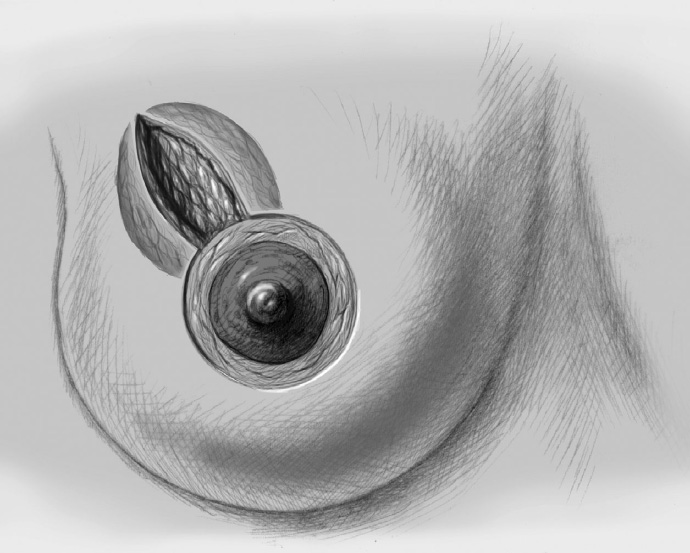

The skin is incised over the tumor region as far as possible (depending on surgeon, tumor size, tumor location, and subsequent treatment). A radial incision may be useful for tumors located in the lower quadrants or directly in the axillary tail of the breast. If the tumor is just beneath the skin, an island of skin over the tumor should be resected also. This can be achieved with both an elliptical semicircular incision and a radial incision. Another form is a purely periareolar incision when the tumor is in a relatively central position (see illustrations below).

The basic decision on whether to use a complex oncoplastic technique is made when the skin is marked preoperatively, with the patient standing or sitting upright. Many surgeons successfully combine the B-plasty incision with periareolar de-epithelialization and excision of a straight or curved ellipse of peripheral skin (Chapter 1.3). When marking the periareolar deepithelialization pattern, an eccentric incision may be necessary to adjust the repositioning of the nipple–areola complex to the anticipated volume displacement.

The periareolar skin is de-epithelialized. Here, too, there are various options. A strip of the most superficial skin layer can be excised with dissecting scissors applied flat or with a scalpel. It is important not to leave behind any surface containing squamous epithelium, but on the other hand the dermis and the important vascular layer beneath it must not be injured. The purpose of periareolar de-epithelialization is to recenter the nipple–areola complex and also to tailor excess skin to the new breast shape following extensive tumor resection.

To cover the defect, the glandular lobes are mobilized from the adjacent parenchyma after subcutaneous dissection. The principle of intramammary lobe creation is to mobilize large parts of the breast (> 25%) either relative to the skin or relative to the pectoralis muscle. This “liberation” of the breast from one of its two planes of fixation allows adequate dissection and rotation of sufficient breast tissue. The Y-flap and rotation flap shown in Chapter 3.2.1 are examples of intramammary dissection.

Central Pedicle—Purely Periareolar Approach

The first step after marking the incision line is periareolar de-epithelialization.

The breast is exposed completely, starting from the wide de-epithelialized ring, by dissecting the skin off it in circular fashion. The skin is elevated from the breast superiorly and inferiorly, leaving a roughly 1-cm layer of subcutaneous fat.